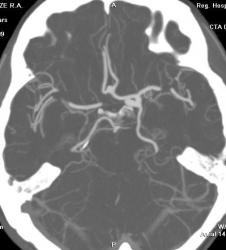

ИзображениеИзображениеИзображениеИзображениеЖенщина, 52 года. Жалобы на птоз слева. Направлена на КТ для исключения аневризмы сифона внутренней сонной артерии (ВСА). Травмы не было.

На КТ правая сонная артерия немного тоньше обычного, сифон продолжается в среднюю мозговую артерию. Правая задняя мозговая артерия отходит от основной артерии.

Левая общая сонная артерия гипертрофирована, на шейном уровне с патологической извитостью. Сифон также шире, чем справа. Задняя мозговая артерия отходит от супраклиноидного отдела ВСА - задняя трифуркация. Левая передняя мозговая артерия делится на две правую и левую передние мозговые артерии (задняя трифуркация), в развилке небольшая аневризма на широком основании. Вторая такая же аневризма на уровне отхождения глазной артерии.

Аневризмы - красные стрелки, Средние мозговые артерии - черные, Задние - зеленые, передняя мозговая - голубая стрелка.